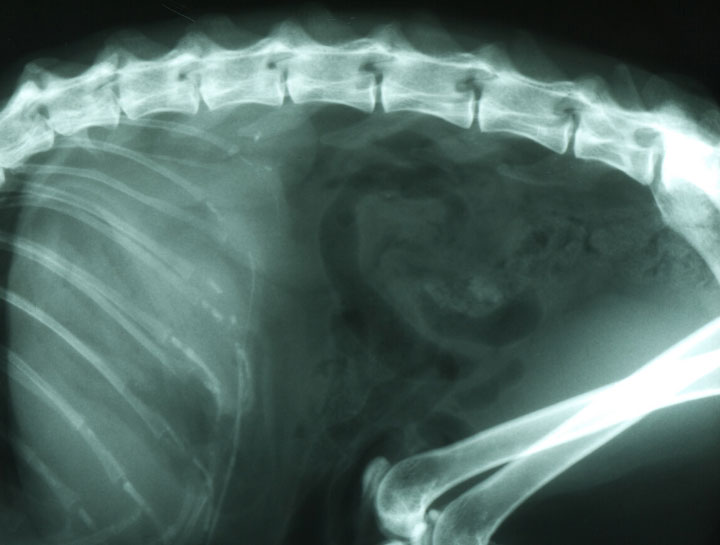

Diagnostic imaging allows us to examine your pet’s internal organs and body systems to better diagnose their conditions. There are different types of diagnostic imaging and the type your pet needs will depend on their symptoms and the affected area of the body.

Pet Digital Radiology

Digital x-rays assist in diagnosing illness & injury.